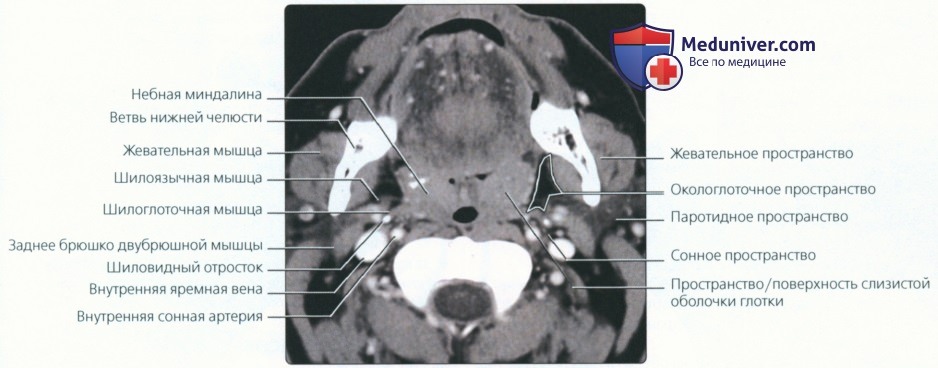

КТ анатомия сосцевидного отростка: особенности и показания